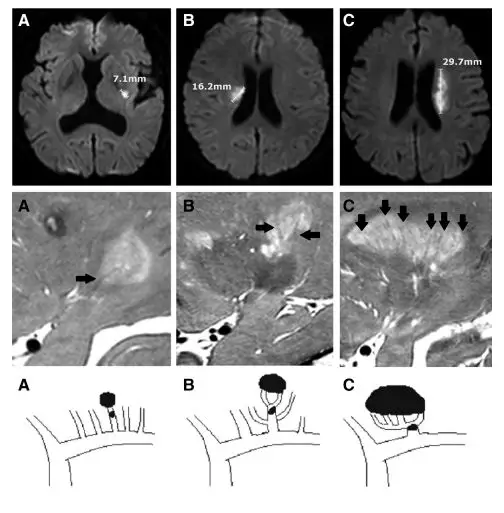

在此篇研究里 , 作者将图3中发自大脑中动脉的血管定义为穿支动脉干(stem) , 再将其下一级血管定义为穿支动脉分支(branch) 。 结果显示 , 单条穿支动脉堵塞 , 如果没有分支 , 梗死直径约7.1mm(图4A);穿支动脉发出2条分支 , 主干堵塞导致梗死灶大小约16.2mm(图4B);穿支动脉分支越多 , 梗死灶越大(图4C) 。

图4 上层示梗死病灶大小;中层示高分辨率MRI展示的穿支动脉分支(黑箭头);C示病变穿支动脉解剖变异

如果只根据梗死灶大小来判定 , 将A和B类梗死称之为腔梗 , 而C类梗死不称为腔梗 , 显然是不合理的 , 因为A、B与C均属于穿支动脉堵塞 。 据此 , 作者证实了他们七年前提出的穿支动脉解剖变异学说 , 也说明采用梗死灶大小诊断腔梗是不合理的 。 整整七年 , Kim团队锲而不舍的研究精神确实值得学习 , 此处应有掌声 。